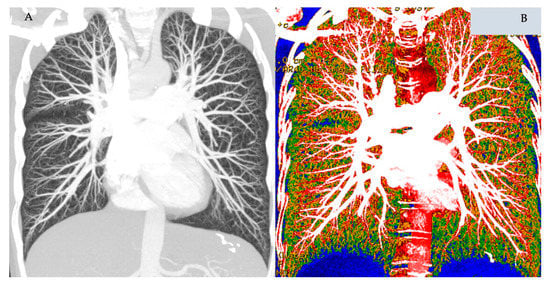

- Winther, H.B.; Hundt, C.; Schmidt, B.; Czerner, C.; Bauersachs, J.; Wacker, F.; Vogel-Claussen, J. ν-Net. JACC Cardiovasc. Imaging 2018, 11, 1036–1038. [Google Scholar] [CrossRef]